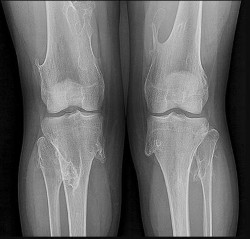

Question 25

A 45-year-old man sustains a high-energy knee injury in a motorcycle accident.

Based on the Schatzker classification, a bicondylar tibial plateau fracture with complete dissociation of the metaphysis from the diaphysis is classified as:

Explanation

A Schatzker VI fracture is defined by complete metaphyseal-diaphyseal dissociation, often accompanied by severe soft tissue injury. Schatzker V is a bicondylar fracture but maintains continuity between the articular segment and the diaphysis. Schatzker I-III involve the lateral plateau, and IV involves the medial plateau.